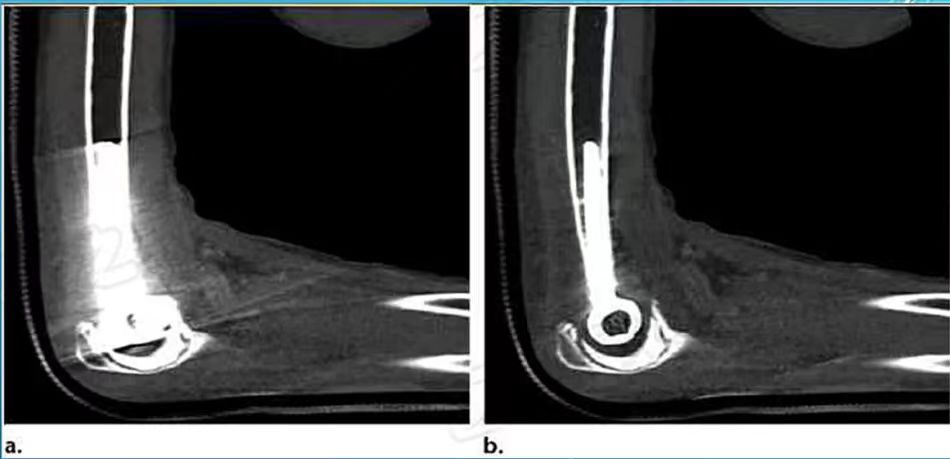

病例三:在四肢关节中应用

可以看到,在肘关节、髋关节、膝关节置换术中,应用单能重建图像伪影降低,金属植入物与周边组织关系清晰。